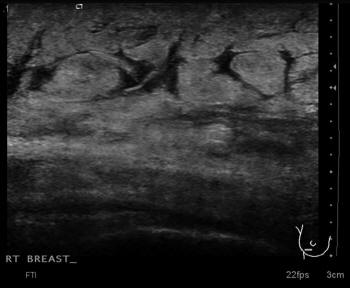

Glandular Tissue Breast Ultrasound

Elevation of the entire breast. At US, hyperechoic glandular tissue is seen extending away from the US scan shows hyperechoic glandular tissue extending away from the retroareolar area Ultrasound of benign breast condi- ... Get Document

Abnormal Tissue Detection Of Breast Ultrasound Image Using ...

Abnormal tissue in ultrasound breast image. Figure 1: The subtle differentiate of glandular tissue in normal breast Figure 2: Sharp cyst inside breast tissue Figure 2 shows an image of sharp cysts. For women between ages 30 to 50, breast cysts are the most ... Retrieve Doc

Breast Ultrasound - Current Technology & Clinical Apps - Reeve

5 9 Breast Ultrasound • Detect and characterize abnormalities within glandular or fatty tissue • Differentiate benign from malignant conditions ... Access Doc